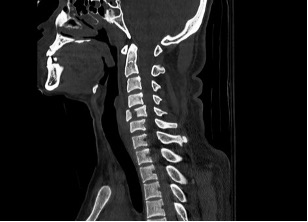

Many people with cervical spine fractures are often diagnosed in the emergency room after a traumatic event such as a car accident, a fall or a sports related injury. A cervical spine fracture can sometimes be seen on an X-ray of the cervical spine but more commonly seen on a CT scan of the cervical spine.